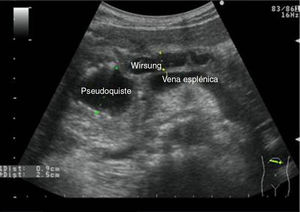

Los diámetros máximos del páncreas varían y son < 3cm para la cabeza y < 2,5cm para el cuerpo y la cola. El conducto de Wirsung (fig. 12) varía entre 1,5mm de diámetro máximo a nivel de la cola y 3mm de diámetro máximo a nivel de la cabeza37.

Escenarios clínicos en atención primaria y evidenciaLa situación clínica más frecuente, en nuestro medio, que nos lleva a realizar ecografía del páncreas, es el dolor en el epigastrio y más si este dolor está irradiado a la región dorso-lumbar; otros escenarios clínicos38 son la ictericia, el síndrome constitucional o las alteraciones analíticas, como la leucocitosis y el aumento de amilasa y lipasa en sangre y orina. A menudo es difícil diferenciar mediante imágenes ecográficas las distintas enfermedades del páncreas, sobre todo entre enfermedades inflamatorias crónicas y enfermedad tumoral (figs. 13 y 14), por lo que habrá que recurrir a pruebas complementarias. El MF debe saber reconocer en las imágenes ecográficas las calcificaciones, las imágenes quísticas o la dilatación de la vía biliar y del conducto de Wirsung (fig. 13), la hiper o hipoecogenicidad (fig. 14) y los márgenes del órgano, entre otros, ya que nos pueden orientar a identificar le lesión que afecta al órgano (tabla 3).